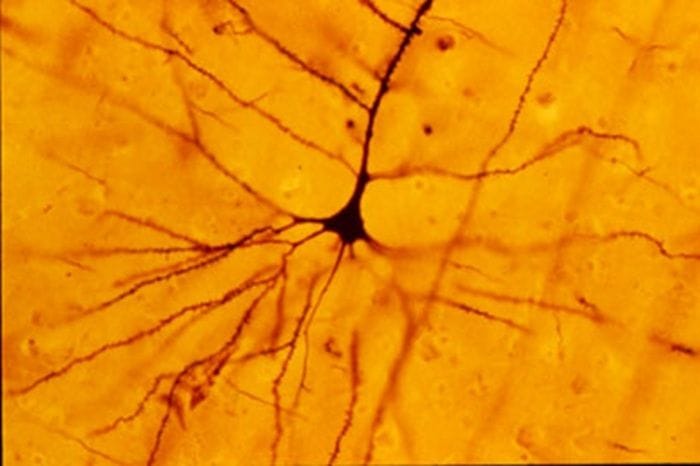

Dalla scoperta dei cosiddetti neuroni specchio , che si attivano sia quando compiamo un'azione sia quando la osserviamo fare a qualcun altro, agli studi che hanno fatto luce sulla malattia di Huntington , un raro disturbo genetico neurodegenerativo per il quale si stanno ora sperimentando possibili terapie. Tanti degli sviluppi compiuti oggi nel campo delle neuroscienze rappresentano l' eredità di Camillo Golgi e della sua ' reazione nera ': la tecnica di colorazione da lui sviluppata nel 1873 , che permise per la prima volta di evidenziare e osservare le singole cellule cerebrali .

Golgi è stato, ad esempio, fondamentale nel lavoro di Giacomo Rizzolatti , neuroscienziato dell'Università di Parma e membro dei Lincei, il cui nome è legato proprio ai neuroni specchio : la loro scoperta, prima nelle scimmie e poi nell'uomo, è considerata una delle principali degli ultimi decenni in questo ambito, per il ruolo decisivo che svolgono nell'apprendimento per imitazione e nel fenomeno dell' empatia .

"Il lavoro di Golgi ha trasformato la capacità di osservare il sistema nervoso ", aggiunge la senatrice a vita Elena Cattaneo, docente all'Università di Milano e lincea, molto nota per le sue pionieristiche ricerche sulla malattia di Huntington. Cattaneo, intervenuta anch'essa al convegno, ha illustrato gli ultimi studi che hanno individuato la firma del disturbo già nel cervello in via di sviluppo dell'embrione e che hanno dimostrato come sia possibile alterare tale firma, in modo da rallentare o fermare la progressione della malattia.